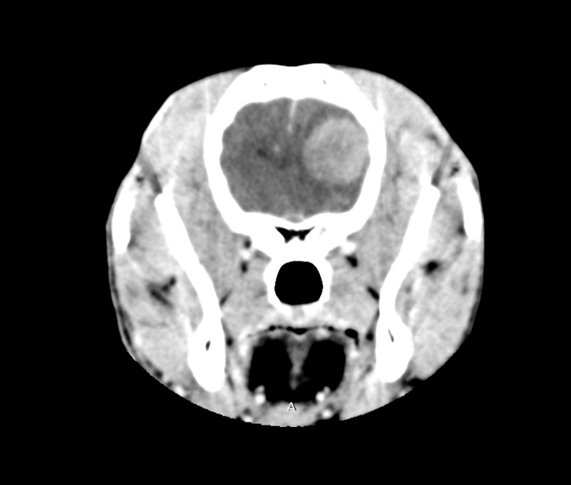

Imagerie médicale

L’imagerie médicale est une discipline transversale nécessaire au dignostic dans de nombreuses pathologies tant en médecine spécialisée, qu’en cardiologie, en neurologie ou en chirurgie.

Neurologie

L’atteinte du système nerveux est difficile à évaluer car les symptômes peuvent être subtiles. La neurologie vétérinaire s’intéresse à l’étude, au diagnostic et au traitement des affections du système nerveux (cerveau, moelle épinière, nerfs périphériques).